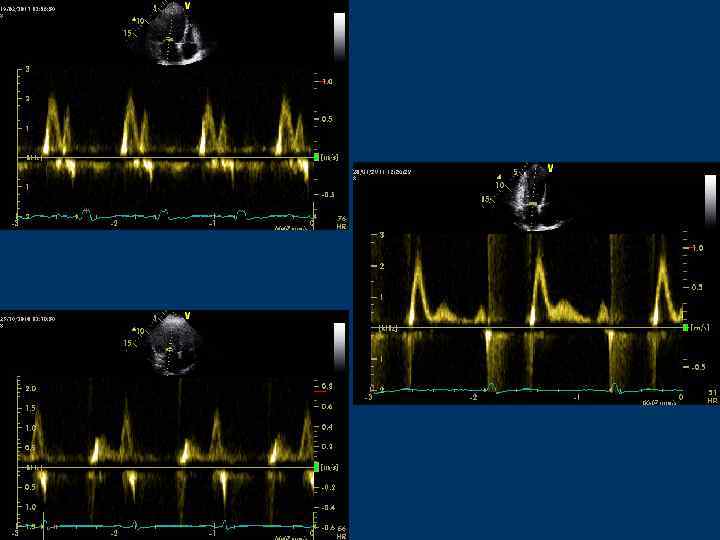

Транстрикуспидальный поток

Транстрикуспидальный диастолический поток Контрольный объем располагают над створками ТК или в области правого фиброзного АВ кольца

Транстрикуспидальный поток Скорость пика Е – 0, 5 м/с (0, 3 -0, 7 )